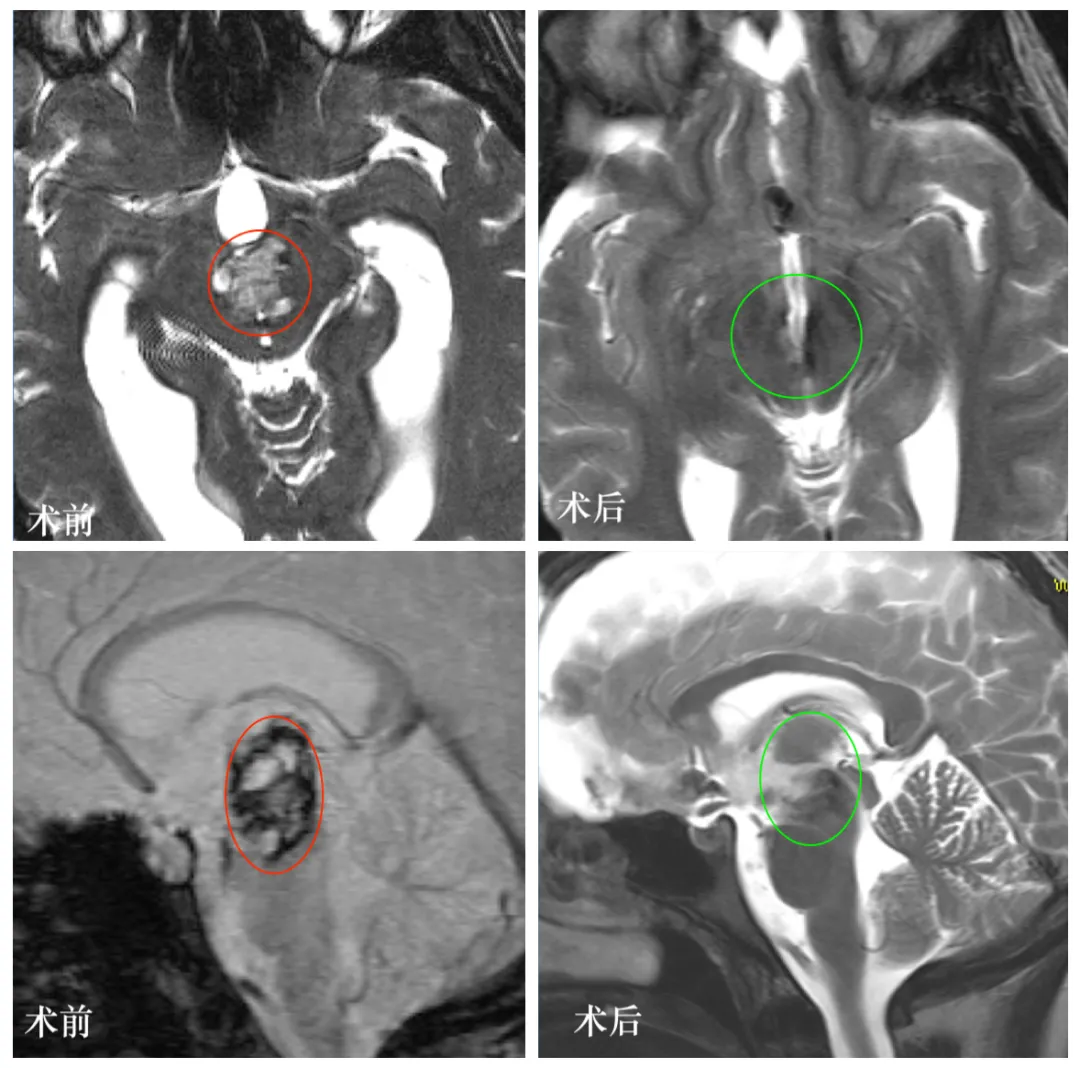

图:Lily颅脑磁共振图像显示中脑区域存在巨大占位性病变,信号混杂,符合海绵状血管瘤影像特征。

图:手术前后颅脑磁共振对比图像,术后影像显示中脑病变已全切,未见脑组织损伤等并发症。

术后2年:Lily已完成大学学业,取得本科学位,工作与生活恢复正常。复查MRI显示病变全切,无复发迹象,无神经功能后遗症。